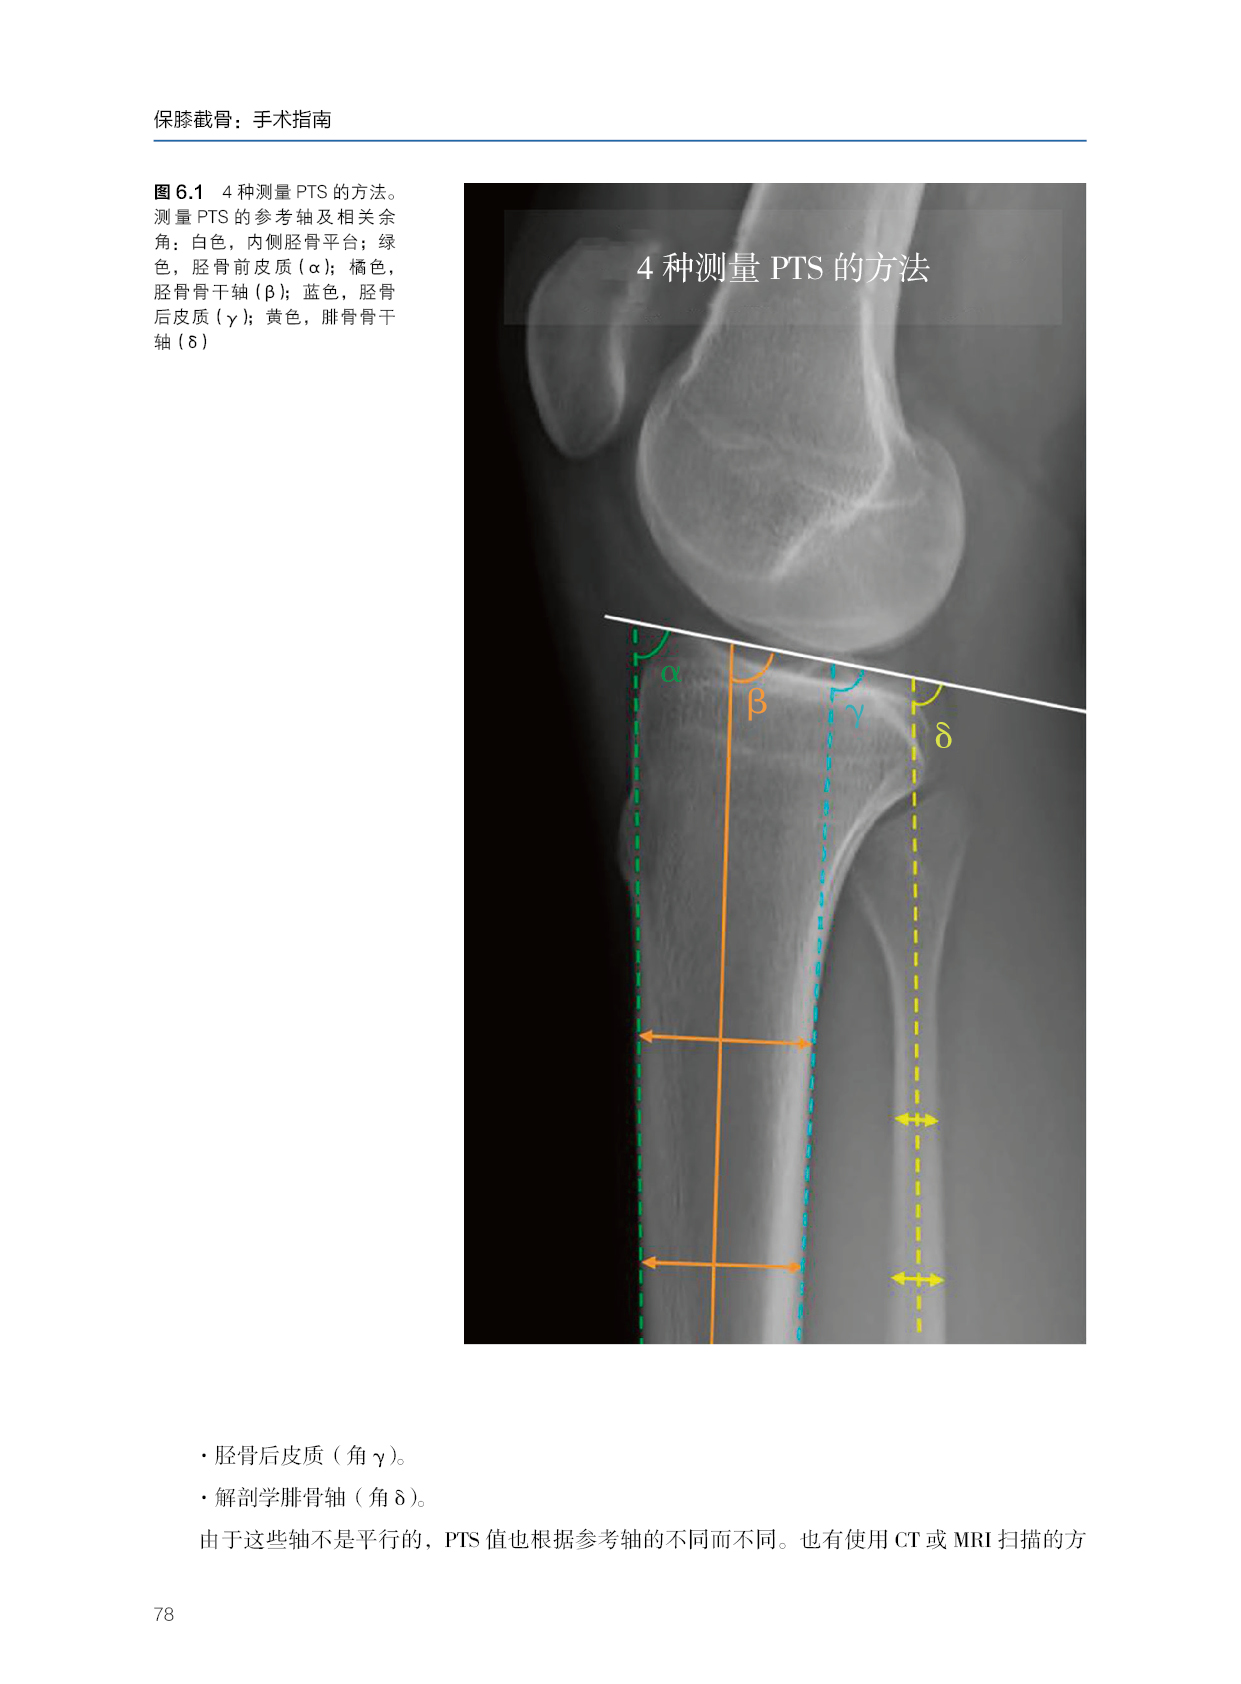

本书是进行保膝手术治疗退行性疾病和畸形相关膝关节不稳定的全面技术指南。根据他们在这些手术中的广泛经验,作者提供了有价值的见解,以确定哪些病人可能受益,以及计划和执行手术的高度精度,并解释可以实现的结果。本书重在介绍膝关节运动损伤的治疗理念。除了大量的真实病例,书中还分享了作者所在医院的整体管理和医生的治疗经验。